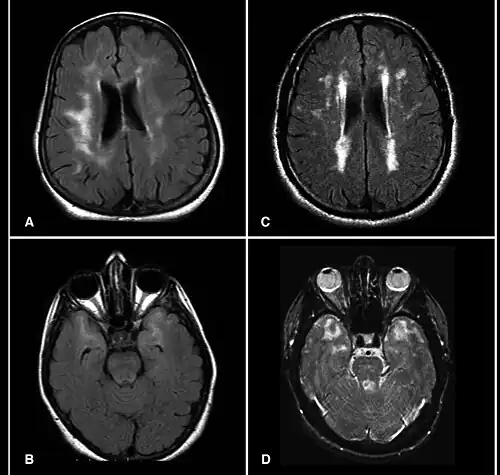

MRI demonstrating white matter changes in the brain of patients with CADASIL

CADASIL is an inherited disorder caused by mutations in the NOTCH3 gene located on chromosome 19.[19] NOTCH3 codes for a transmembrane protein whose function is not well-known. However, the mutation causes accumulation of this protein within small to medium-sized blood vessels.[19] This disease often presents in early adulthood with migraines, stroke, mood disturbances, and cognitive deterioration. MRI shows white matter changes in the brain and also signs of repeated strokes. The diagnosis can be confirmed by gene testing.[20]